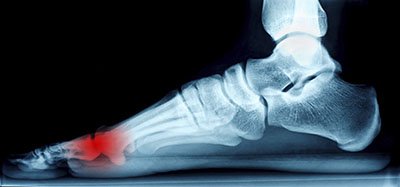

Morton’s neuroma may develop when the tissue around one of the nerves leading to your foot begins to thicken. When this occurs, you may experience some discomfort as if you were standing on a pebble stuck in your shoe. Most symptoms will not appear outwardly and will be experienced in the form of a sharp, burning pain in the ball of the foot, as well as a stinging or burning feeling in the toes that may sometimes lead to numbness.

Treatment for Morton’s Neuroma will often vary, depending on the severity of a patient’s condition. In some cases, injections may be helpful for alleviating pain. Another form of treatment is decompression surgery, in which a podiatrist will work to alleviate the pressure on the nerve. In more severe cases, full removal of the nerve would be required.